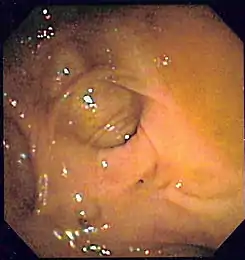

Colonoscopia

Es el método diagnóstico inicial más indicado para la mayor parte de los pacientes.[95][107] Consigue el diagnóstico entre el 75 y el 100% de los casos (con un 91% de media).[108] Y además ofrece la posibilidad de hacer tratamiento de la lesión. La potencia diagnóstica de la colonoscopia es mayor que la del resto de métodos diagnósticos radiológicos, ya que estos requieren que haya sangrado activo en el momento del examen.[17][4]

• Momento de realizar la colonoscopia: Tradicionalmente, la colonoscopia se realizaba de forma electiva tras la resolución de la HDB. Desde hace tiempo la tendencia ha cambiado y actualmente las guías de práctica clínica para el manejo estándar de la HDB que precisa manejo urgente hospitalario recomiendan la colonoscopia precoz, es decir, aquella realizada alrededor de las primeras 24 horas del ingreso.[107][4] Sin embargo, el momento óptimo de su realización todavía no se ha establecido con el suficiente consenso. Los estudios indican que la colonoscopia precoz ofrece ciertas ventajas con respecto a la colonoscopia electiva: aumenta la rentabilidad diagnóstica con un mayor número de diagnósticos de certeza (un 88-27% frente a la electiva que consigue un 48-22%),[112][113] disminuye la morbilidad, disminuye la necesidad de transfusión de hematíes, disminuye la necesidad de cirugía, disminuye la mortalidad, y disminuye la estancia media hospitalaria.[114][36][109][115] En algunas patologías también tiende a disminuir las recurrencias del sangrado. En un estudio del 2003, ya citado, el grado de éxito de la endoscopia disminuía conforme se demoraba su realización, siendo del 29% si se hacía en las primeras 12 horas, del 13% si se hacía entre las primeras 12 y 24 horas, del 4% si se hacía entre las 24 y las 48 horas, y del 0% si se hacía pasadas 48 horas.[112] No obstante, algunos estudios no han podido demostrar de forma concluyente que en todos los casos la realización urgente de una colonoscopia mejore todos los resultados clínicos comentados o el coste hospitalario comparado con aquellos en los que la realización de la colonoscopia fue electiva o se demoró.[113][110]

Para determinar la certeza de haber encontrado la localización o lesión de la hemorragia se aplican una serie de criterios diagnósticos endoscópicos, que están basados en los utilizados en la endoscopia de la HDA. Estos criterios vienen descritos en la tabla 4.

Tabla 4. Criterios diagnósticos endoscópicos de localización de la hemorragia en el colon (Zuckerman y Prakash 1998,[6] Green et al. 2005[113])

Grado de probabilidad Tipo Criterio

Definitivo 1 Lesión con hemorragia activa: visualización de emanación activa de sangre de un lugar específico o de una lesión fácilmente identificable, hemorragia que persiste a pesar de haber irrigado profusamente la zona.

Definitivo 2 Lesión no hemorrágica con vaso expuesto visible: lesión muy localizada protuberante de coloración púrpura o roja.

Definitivo 3 Lesión con coágulo adherido: coágulo denso y adherido que persiste a pesar de lavado profuso del mismo.

Presuntivo 4 Sangre reciente localizada en un segmento determinado del colon situado en la misma localización que una lesión potencialmente sangrante o distal a dicha lesión.

Presuntivo 5 Divertículo ulcerado con sangre reciente en una zona próxima.

Probable 6 Ausencia de sangre reciente en íleon terminal con sangre presente en el colon.

Como un alto porcentaje de hemorragias bajas ceden espontáneamente, hay muchos diagnósticos endoscópicos dudosos cuando no se identifica una lesión hemorrágica activa o un coágulo adherido evidentes. Es frecuente, por ejemplo, que se vean varios divérticulos y además una angiodisplasia, o unas hemorroides internas congestivas, sin signos de sangrado ni coágulo adherido en ninguna de estas lesiones. En ocasiones, será la presencia de sangre en un nivel u otro del colon junto con las lesiones potencialmente sangrantes lo que nos determine la impresión diagnóstica.[7]